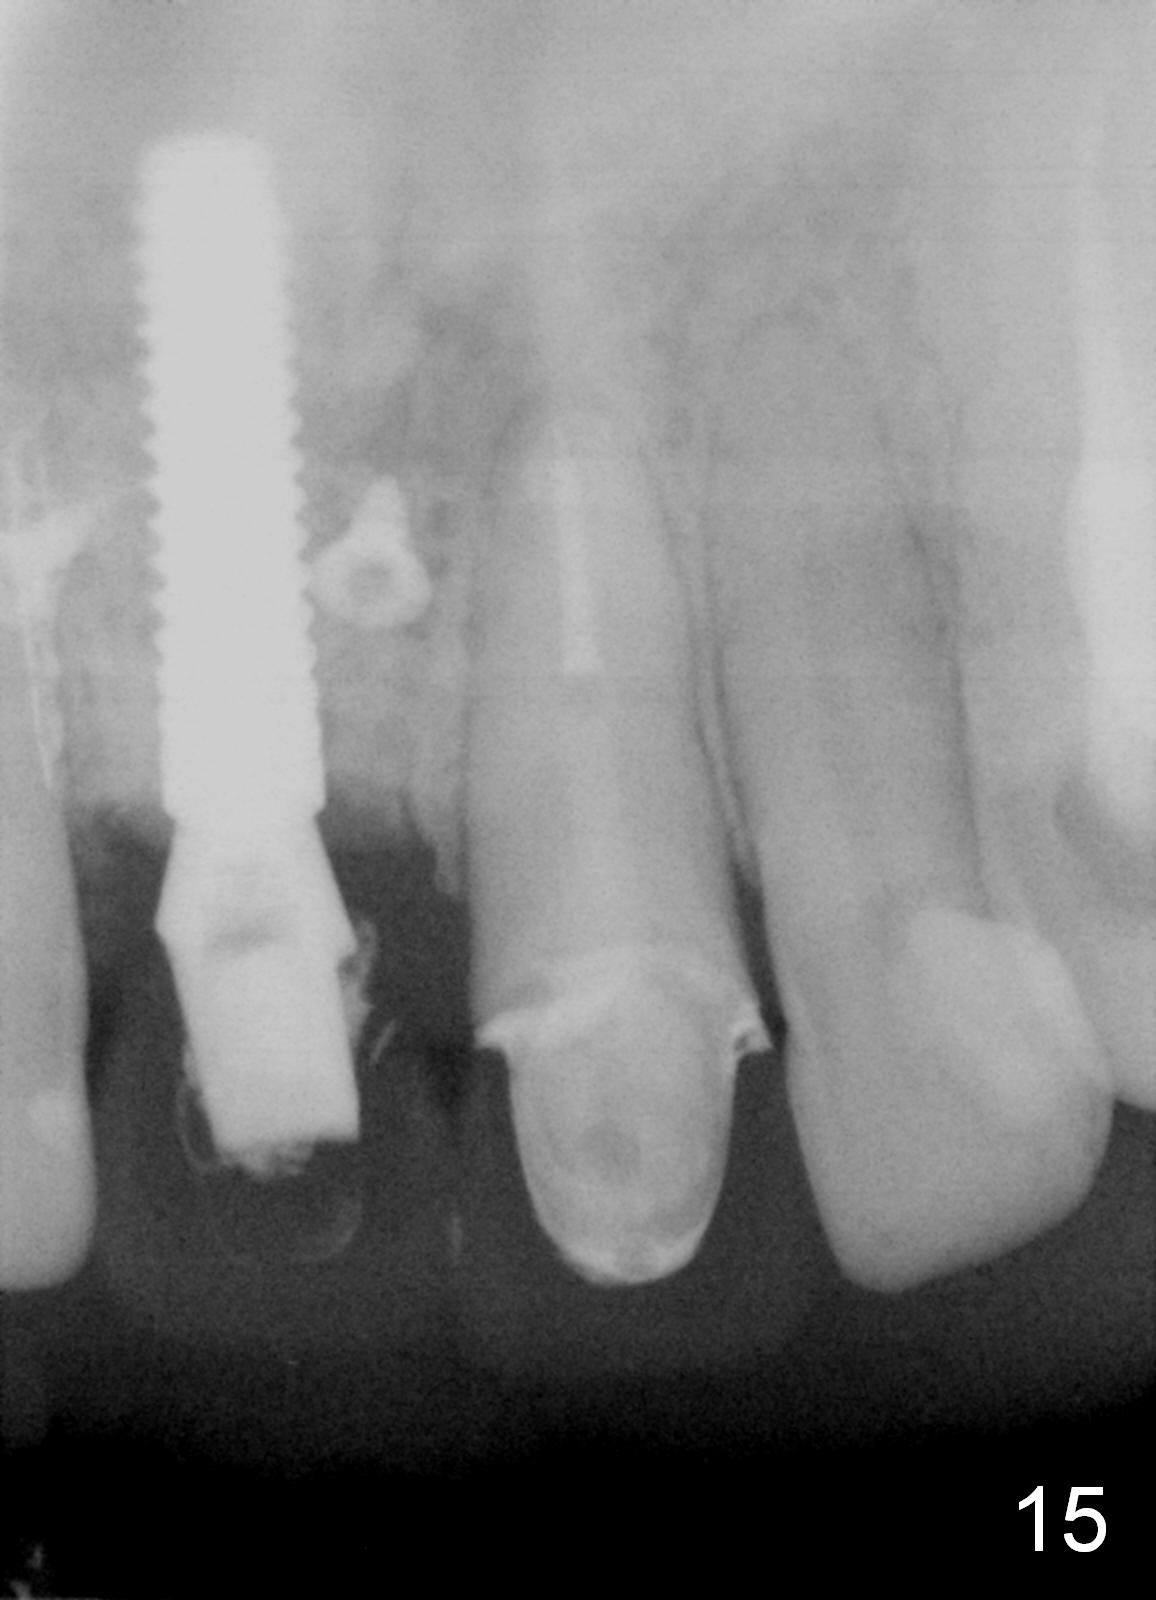

To correct the gingival margin associated with #8 implant, bone graft is needed.  Particulate graft may not stay in place. Chin graft is harvested.  Since the roots of the lower anterior teeth are long (Fig.8), the width of the chin graft is limited for direct screw fixation (Fig.9,10).  Titanium mesh is used for fixation of the graft.  Connective tissue graft from the palate is to increase bulk at the site of #8 (Fig.11 *).  There is no symptom or sign of infection 1 month postop (Fig.12,13).  Although there is alteration of sensation of the lower incisors, there is no apical radiolucency of them 4 months postop (Fig14).  There is no abnormality associated with the bone graft and Titanium mesh (Fig.15).